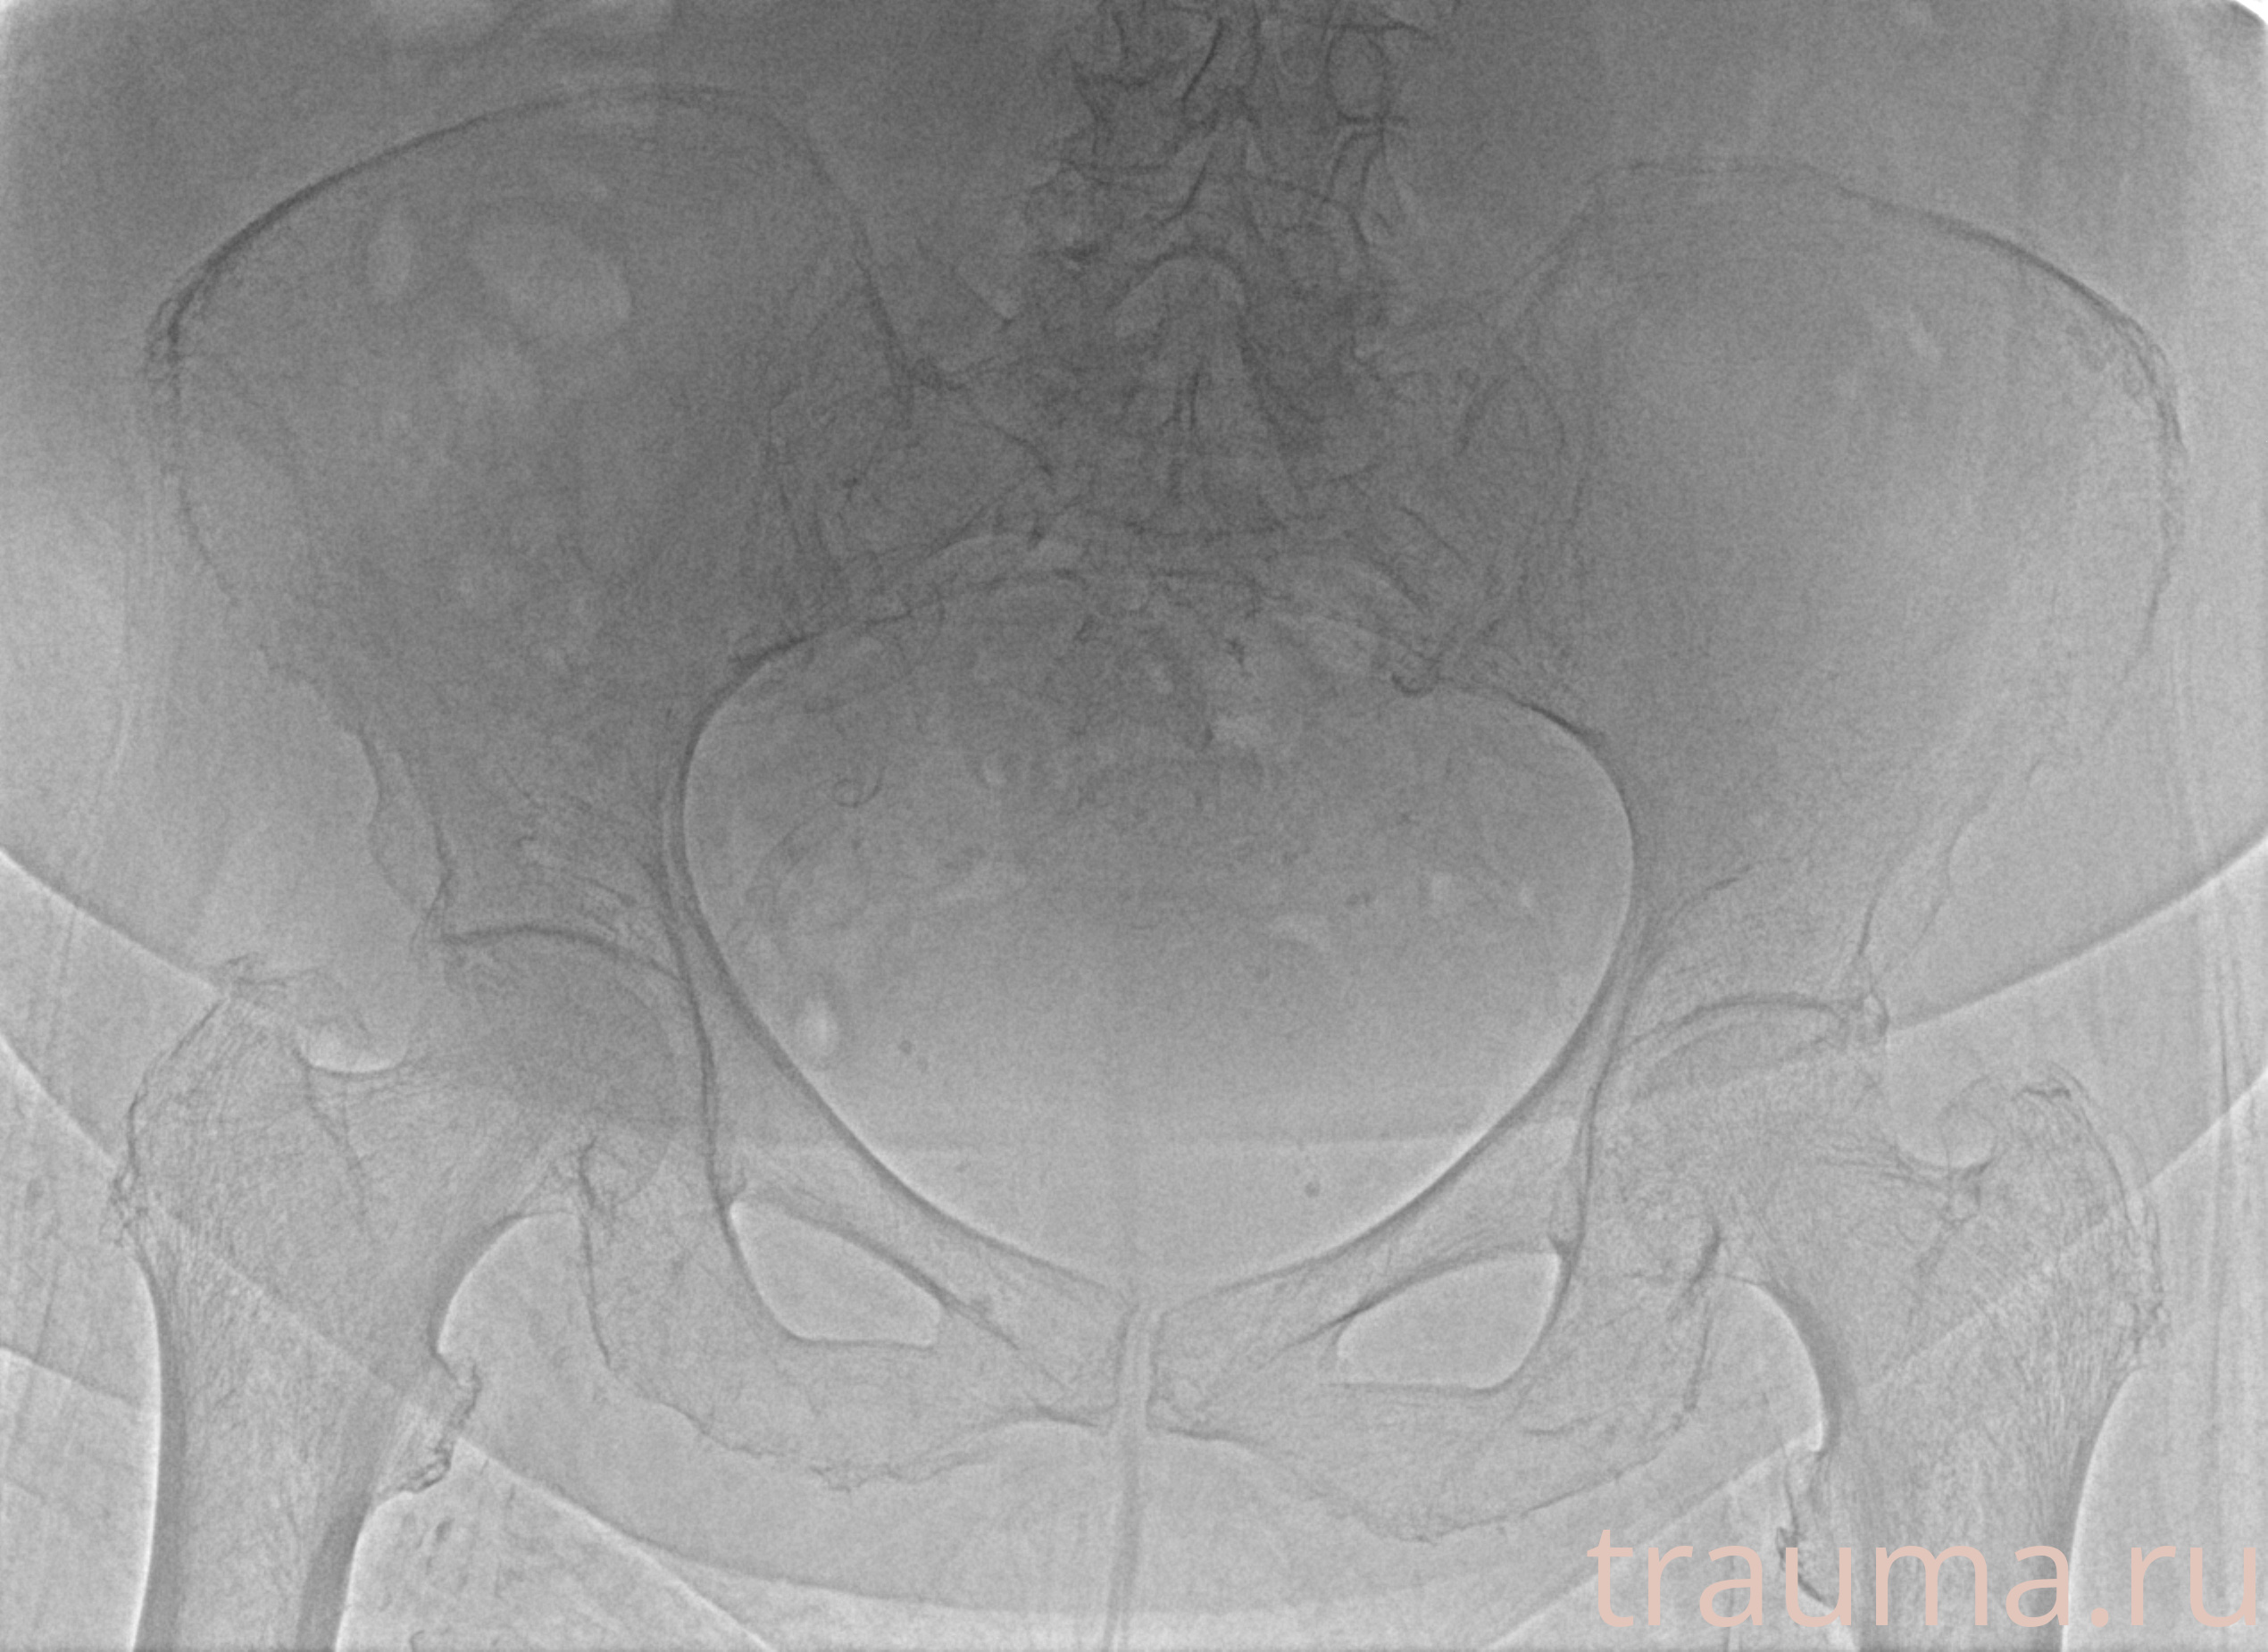

Рентгенограммы

Рентген на дому: по вашему адресу приезжает врач-рентгенолог, травматолог-ортопед с мобильным рентгеновским аппаратом, проводит диагностику травмы или заболевания, делает необходимые рентгенограммы, дает рекомендации по дальнейшему лечению. Получить качественные снимки в домашних условиях возможно благодаря уникальной методике, разработанной МосРентген Центром для института  Склифосовского